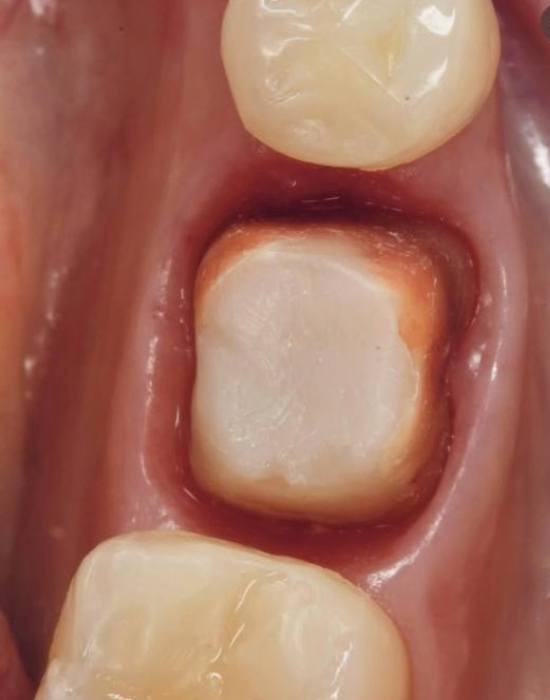

✅ Протокол лікування. Клінічні приклади

• Вертикальне препарування, полірування

• Ремоделювання м’яких тканин та стабілізація ясен

• Повторна ретракція, сканування та остаточна реставрація

• Функції тимчасової коронки: стабілізація коагуляту; формування ясенного контуру; контроль компресії тканин

• Профіль виходу коронки: трансгінгівальний контур; компресія тканин; адаптація ясен